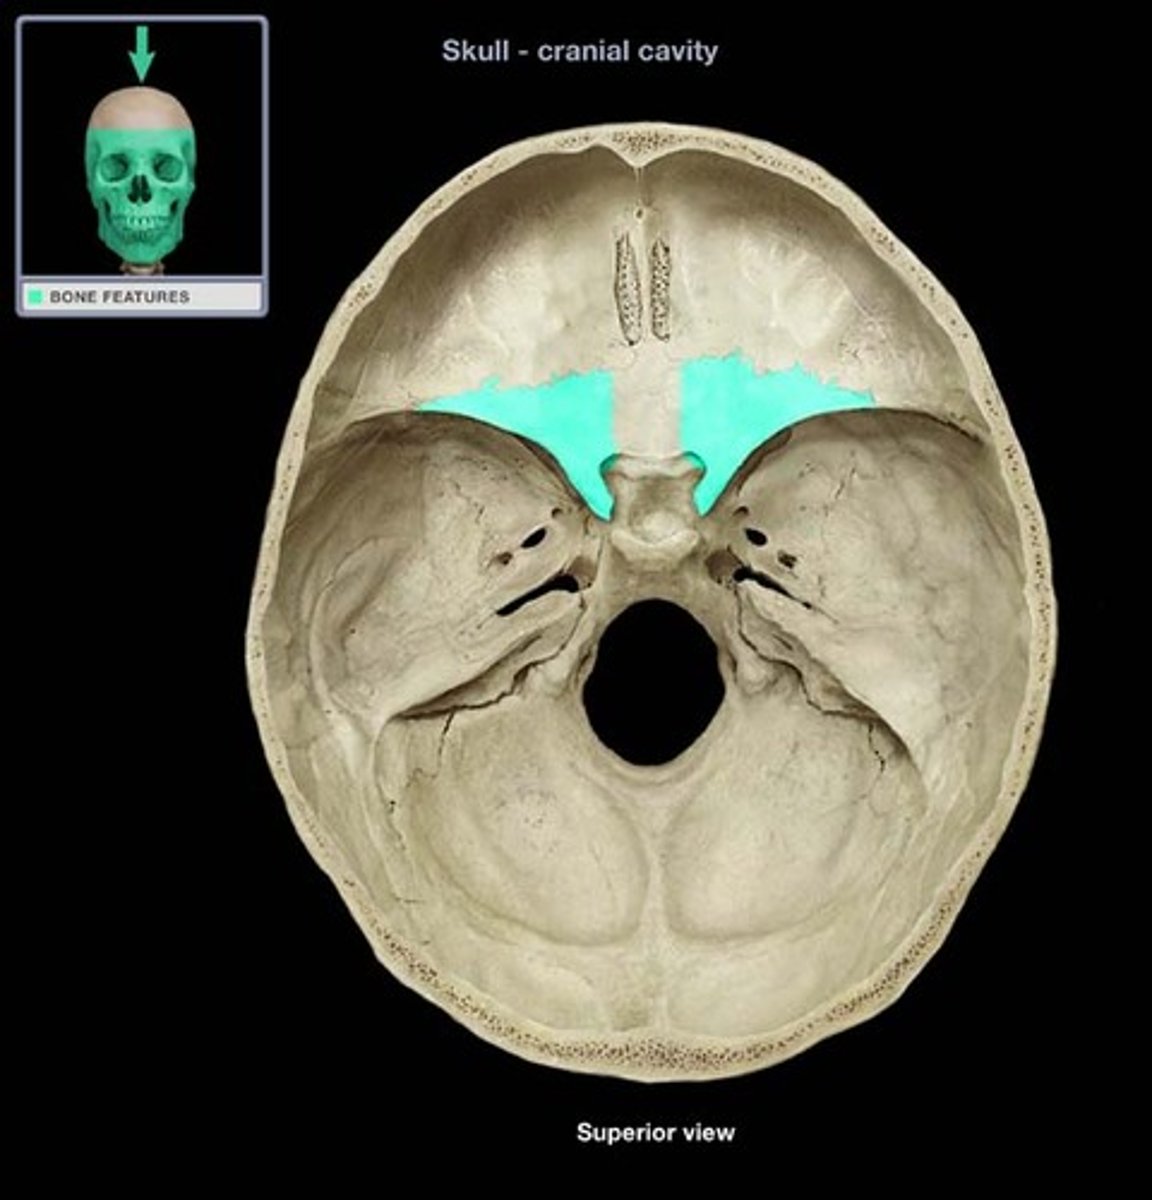

Sella turcia (hypophyseal fossa)